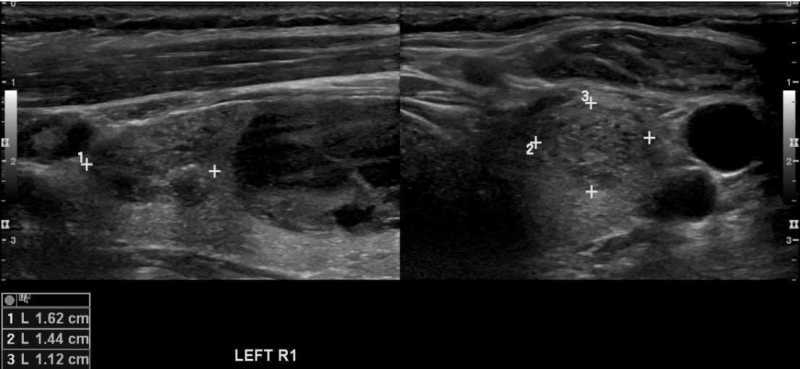

Example 2

What is the TIRADS score for this nodule?

TIRADS example 2 RadioGyan.comTIRADS example 2 RadioGyan.com

Answer:

2 points – Solid

2 points – Hypoechoic

0 point – Shape: Wider than tall

0 point – Ill-defined margin

0 Point – No echogenic foci [e.g. calcification)

Total 4, 5 or 6 points = TIRADS 4 nodule; Risk of neoplasm 5-20%